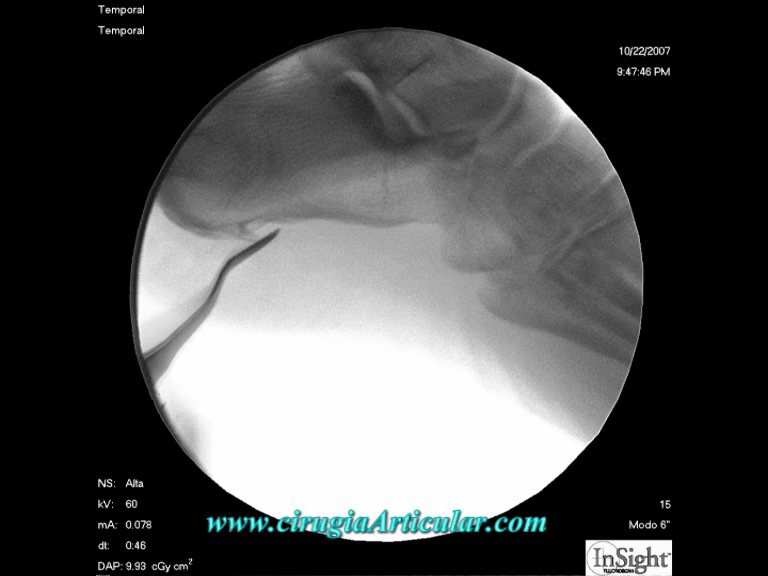

Foto 4

En primer lugar se realiza un sección de la fascia plantar que se ancla en este punto. Controlaremos todas las acciones mediante rayos – x. |